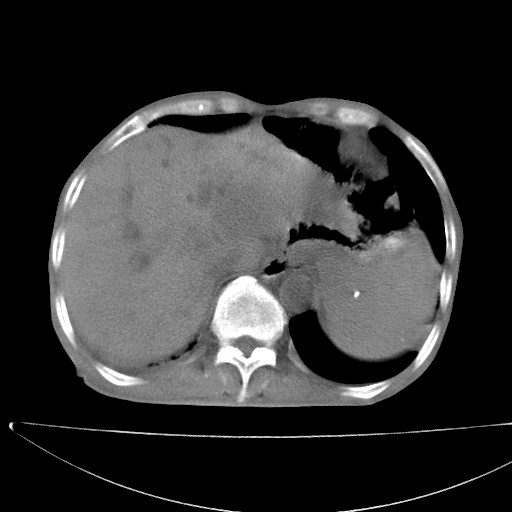

患者男70岁,上腹部不适1月。8年前有胃癌手术史。余病史不祥。

1)胃癌术后,复发不排除。

2)肝脏转移瘤。

3)肝脏钙化灶。

5)腹膜后多发性淋巴结转移。

6)腹水。

1)胃癌术后,不排除复发可能。2)考虑肝脏及腹膜后淋巴结转移瘤。3)肝内胆管扩张,胆囊增大。4)肝内胆管结石(或钙化)。5)脾脏钙化灶。6)腹水。7)右侧少量胸腔积液。

1、胃癌根治胃空肠吻合术后,残胃癌?

2、肝门区占位性病变并胆道上段梗阻(肝内胆管扩张、胆囊增大),考虑肝门区淋巴结转移累及胆总管,建议ct增强扫描;

3、右侧胸腔少量积液、少量腹水;

4、肝右叶胆管结石。

肝门区占位性病变并肝内胆管扩张。

小网膜囊区及腹膜后肿大淋巴结。